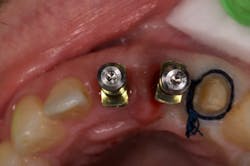

I began centering my consultation appointments on options that subsequently allowed patients to actually sell themselves on the implant treatment modality. I would present the tooth-replacement options of endo/core/crown, extraction/bridge, and extraction/implant ... and then I would explain the pros and cons of each. What I found is that patients overwhelmingly chose the root-replacement option—dental implants—over the old-school (drill-o-dontics) to reconstruct their missing tooth. Patients actually wanted an implant once they were armed with all the complete information they needed to make their decision. Having models on hand that show the difference between each option is highly effective, especially for those patients who are visual learners.

This is the paradigm shift in thinking that initiated big changes in my practice. In 2010, my little office restored 38 implant fixtures. By 2017, we were restoring closer to 200. What a difference! When patients began to realize they had treatment possibilities that may have a better long-term prognosis than the traditional replacement options, implants became a definite green light for them.